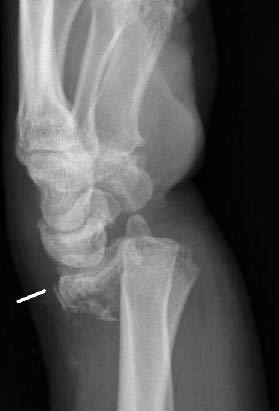

The diagnostic imaging includes standard PA and lateral radiographs. When reviewing these plain radiographs, one should pay close attention to the space between the individual carpal bones on the PA view. The space between the bones should be uniform. The presence of a gap greater than 2 mm is indicative of ligamentous injury and possible carpal instability.32 Gilula described radiographic lines for discovering carpal bone injuries due to ligamentous and bony injuries of the wrist.33 In an uninjured wrist, the articular surfaces of the proximal and distal carpal rows form smooth arcs at the radiocarpal and midcarpal articulations.32 (See Figure 6.) A disruption of any of these lines is indicative of carpal instability or possible injury.32 The lateral view of the wrist is often the best view to appreciate a perilunate dislocation. Remember the "3 Cs" sign when examining a lateral radiograph of the wrist. The "3 Cs" are formed by the articulations of the distal radius, lunate, capitate, and base of the third metacarpal, respectively. (See Figures 7 and 8.) The arrangement of the 3 Cs in a perilunate dislocation is disrupted at the level of the capitate, which represents the third C. It is displaced dorsally toward the lunate, which remains in contact with the radius.12 (See Figure 9.)

Figure 7: Normal Wrist Lateral Radiograph

Figure 8: Relationship Between the Distal Radius Surface, Lunate, and Capitate on the Lateral View